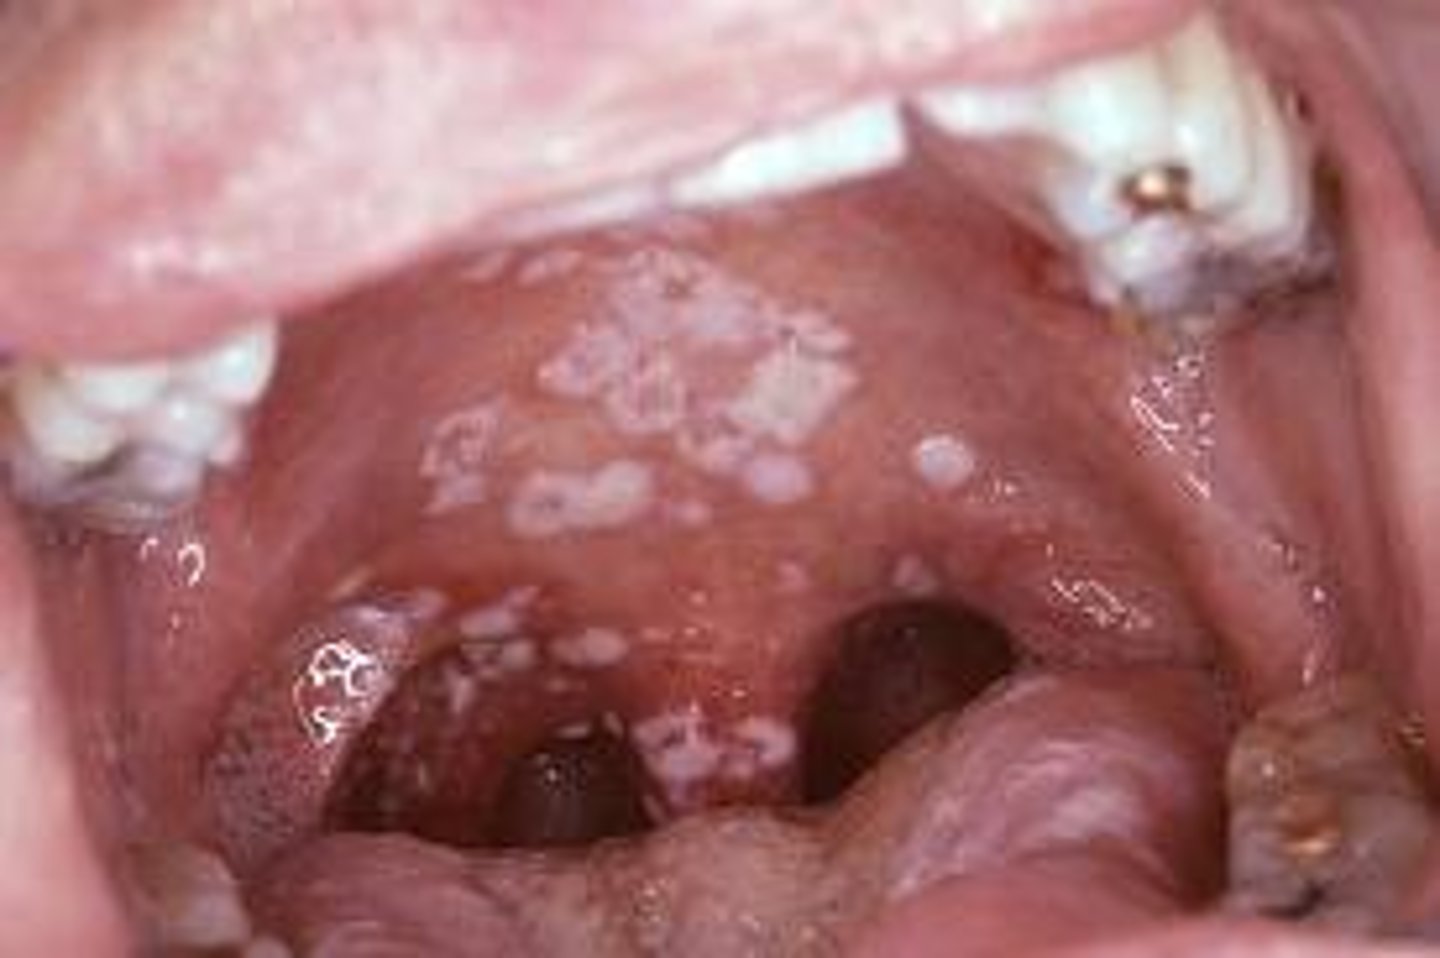

Candidiasis

yeast infections occurring on the skin or mucous membranes in the warm, moist areas such as the vagina or the mouth often caused by the fungus Candida